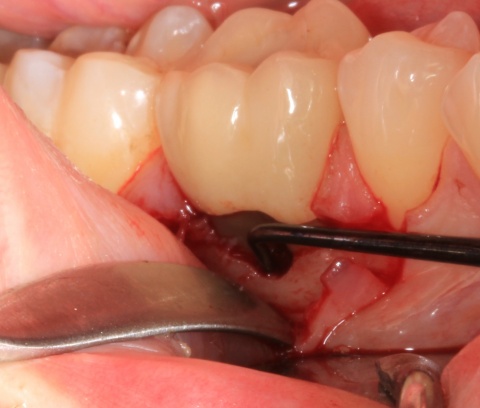

Eine Schnittstelle zu den bereits ausgeführten parodontalen Voraussetzungen des Zahnerhalts ergibt sich bei kombinierten Paro-Endo-Läsionen beziehungsweise Endo-Paro-Läsionen. Zeigen konservative Behandlungsansätze bei den meisten dieser Befunde gute Ergebnisse, ist bei einem lokal ausgeprägten Knochenabbau zumeist die chirurgische Intervention zum Zahnerhalt notwendig (Abb. 11 und 12). Wichtig dabei ist die Unterscheidung der primären Ursache (primär endodontische oder primär parodontale Ätiologie) der Läsion und einem dieser Ursache angepasstem Behandlungsprotokoll.